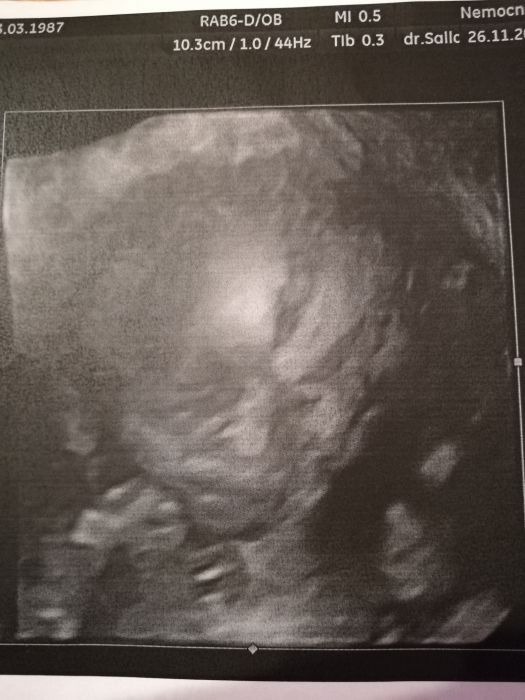

Holky, dopadli jsme na jednicku. Vypada to fakt na tu holcicku, tak mame radost. Krasne nam roste s vse ma v poradku, velikosti je dokonce o den napred. Vaha cca 400g. V pondeli jdeme na srdicko a posledni screening mame 30.1.19. Fotky nejake mam, tak vam je sem potom taky hodim.